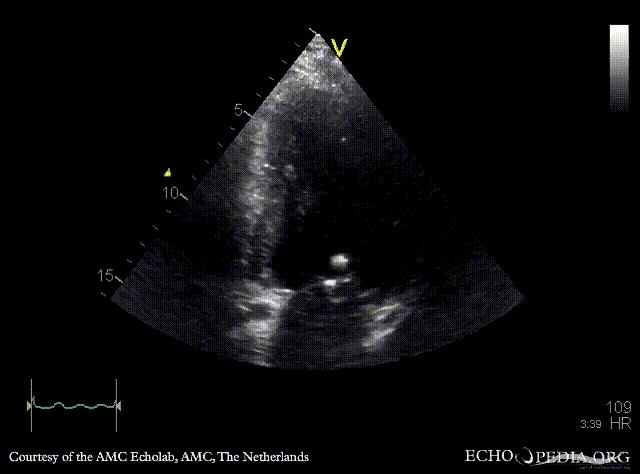

| PLAX: vegetations on PMVL | A4CH |

| A4CH: Color Doppler, severe mitral regurgitation, excentric jet | |